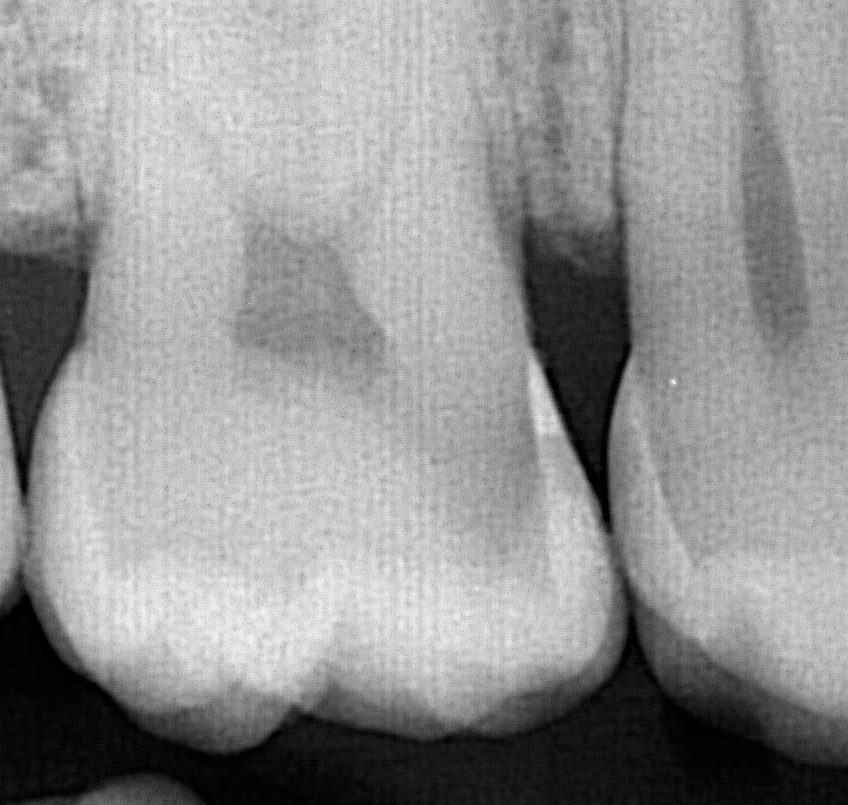

2. The Dental Filling is too close to the nerve

When a Cavity is very deep, the dentist has to drill close to the nerve. The nerve doesn’t always respond well to the drilling if its too close. Placing a filling very close to the nerve can also cause the nerve to act abnormally or the nerve can die off over time. It’s best to take x-rays of deep dental fillings routinely to make sure the tooth is healthy. Symptoms of a tooth with a deep filling such as throbbing pain or lingering sensitivity to hot or cold lasting 15 seconds or longer, signify the tooth likely needs a root canal.